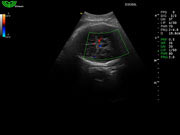

Система поддерживает СFM-режим, PW-режим, CW-режим, режим направленного энергетического потока, режим Color-M, панорамный режим, ECG, DICOM 3.0 и универсальные пакеты программ для кардиологии, сосудистого исследования и акушерства.

Режимы изображения: B, 2B, B/M, B/BC, CFM, PW, HPRF, PD, направленный PD, CW, режим Color M.

Дополнительные возможности: триплекс, трапециидальное отображение, анатомический М-режим, «free-hand» трехмерная реконструкция, авто-доплер.